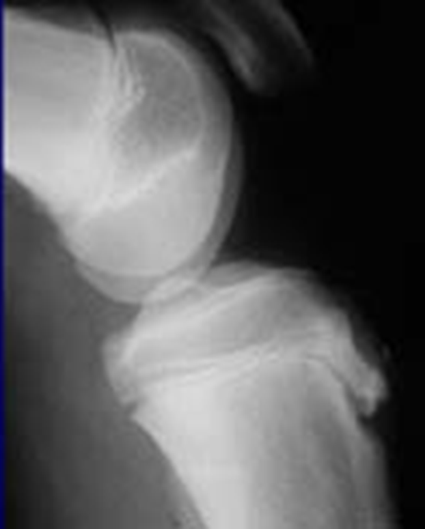

Trauma and Non-Trauma Lateral Knee (Mediolateral)

•Evidence of proper collimation and the presence of a side marker placed clear of the anatomy of interest

•Knee flexed 20 to 30 degrees in true lateral position as demonstrated by femoral condyles superimposed (locate the more magnified medial condyle)

•Anterior surface of medial condyle closer to patella results from over-rotation toward the image receptor (IR).

•Anterior surface of medial condyle farther from patella results from under- rotation away from the image receptor (IR).

•Inferior surface of medial condyle caudal to lateral condyle results from insufficient cephalad central ray (CR) angle.

•Inferior surface of lateral condyle caudal to medial condyle results from too far cephalad CR angle.

•Fibular head and tibia slightly superimposed (over rotation causes less superimposition, and under rotation causes more superimposition)

•Patella in a lateral profile

•Open patellofemoral joint space

•Open joint space between femoral condyles and tibia

•Bony trabecular detail and surrounding soft tissues

over-rotated fibular head is not touching

Patellofemoral joint space is not open (Condyle is in it)

Remove soft tissue of another leg

The medial condyle is closer to the patella it is over rotated

Lateral condyle is lower, too much tube angle

Rotation, fibula is under! Which means it is under-rotated. The condyle is in the patella femoral space, the abductor tubercle (medial condyle) , medial condyle is posterior. Central Ray is too superior. NOT ENOUGH